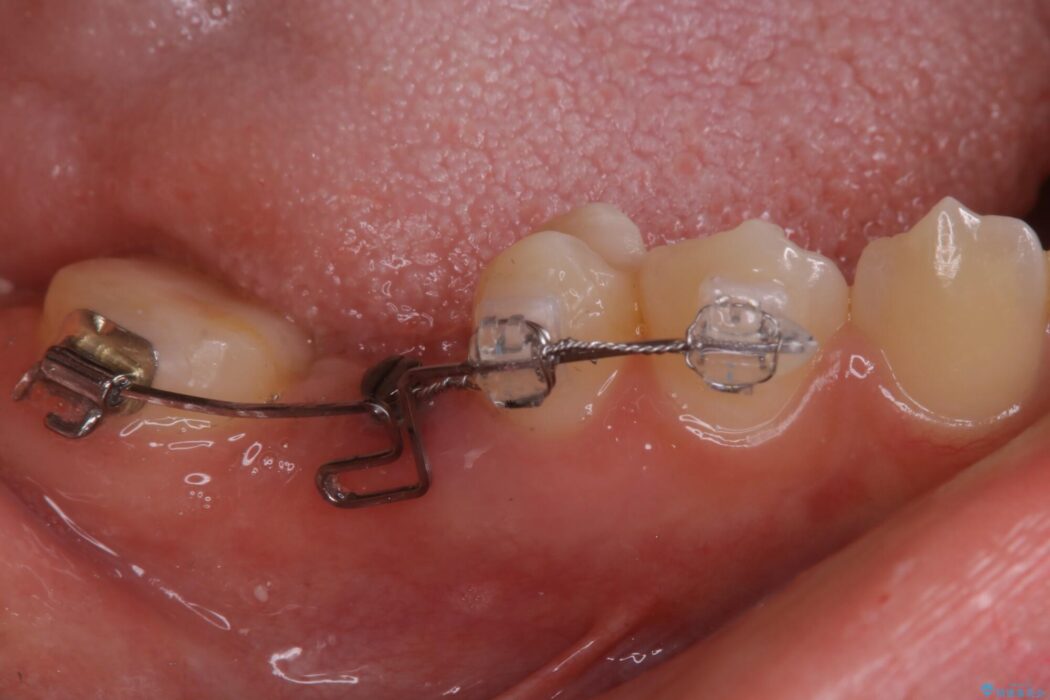

診査した結果、欠損した状態で長期間放置していたことが原因で最高峰の奥歯が欠けた部分に向かって傾斜してしまっていました。

この状態のままブリッジ治療へと進んでしまうと神経が露出する可能性が否定できないため、まずワイヤー装置による部分矯正で歯軸を通常位置へ戻してから補綴治療を行うこととしました。

本症例では、健康な歯を可及的に守るため神経の処置を避けた上で部分矯正を併用して行うことにより、安全に補綴治療(ブリッジ)ができました。